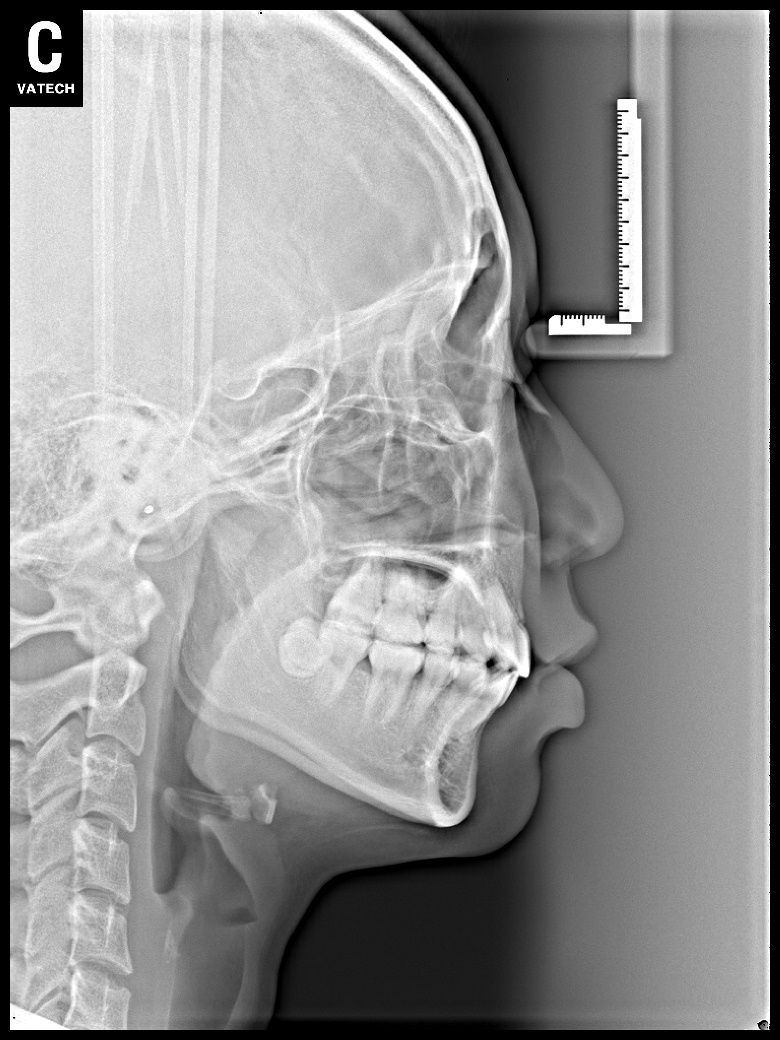

치료 전 사진입니다.